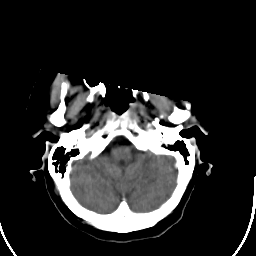

Stroke CT #1 -- Slice #3

[Home][Help][Clinical] Slice 3